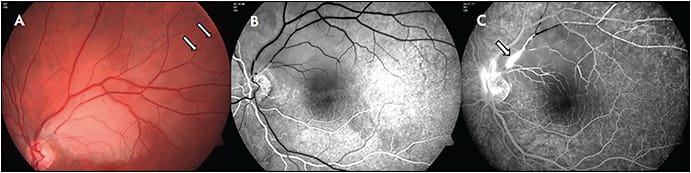

A study by the European Susac Consortium6 describes established criteria for diagnosis of either definite or probable Susac syndrome. In definite Susac, patients present an unequivocal clinical and/or paraclinical involvement of all 3 main organs (fulfilling the typical clinical triad). Cerebral involvement includes new cognitive impairment and/or behavioral changes and/or new focal neurological symptoms and/or new headache, and typical cranial MRI findings. The MRI findings include multiple small hyperintense foci on T2-weighted images, with contrast-enhancing lesions in white and gray matter both supratentorially and infratentorially and with corpus callosal and leptomeningeal involvement. These lesions can appear as “snowballs.” Callosal lesions involving the central fibers are considered pathognomic for Susac syndrome in the appropriate clinical setting, and occasional linear stranding from these areas may be seen.7 Retinal involvement includes branch retinal artery occlusion (BRAO) or arteriolar wall hyperfluorescence (AWH) or signs of branch retinal ischemia in fluorescein angiography (FA) (Figure 1). To note, the presence of AWH remote from retinal vascular injury may confirm diagnosis, because it has never been described in any other condition.8 Vestibulocochlear involvement includes new tinnitus and/or sensorineural hearing loss and/or peripheral vertigo, supported by objective testing.9

Signs of retinal involvement in Susac syndrome fall along a spectrum from symptomatic and funduscopically obvious BRAO to subtle asymptomatic peripheral involvement evident only on FA. Funduscopy may reveal Gass plaques, ie, yellow refractile lesions, simulating emboli. These are most probably caused by an immune-mediated localized reaction in the retinal arterial wall. In contrast to thrombin or cholesterol plaques, Gass plaques may be present in any arterial location and are not limited to the arteriolar bifurcation. In acute BRAO, typical sectoral whitening due to ischemia can be visible.10 Neovascularization and vitreous hemorrhage due to retinal ischemia are rare complications. In the later course of the disease, arterioarterial or arteriovenous collaterals may occur.11

Visual field tests are a valuable tool to detect, quantify, and monitor visual field defects. These include altitudinal defects, paracentral scotoma, or central scotoma. Fundus FA is the diagnostic pillar in the workup for suspected Susac, as well as in the monitoring of treatment response and titration of therapy, even with normal funduscopy in asymptomatic patients. Susac syndrome may involve the retinal arteries from their large proximal branches up to small capillaries in the far periperhy. Fluorescein angiography can demonstrate BRAO already in the early frames, and BRAO can range from complete occlusion to only partial involvement. Arteriolar wall hyperfluorescence may accompany BRAO or be present in the absence of BRAO.12 Of note, AWH may not be evident in early photos but often becomes evident by mid and late frames. The extent of capillary nonperfusion becomes most clearly evident on late images. Recently, our group described microaneurysms as sequelae of peripheral ischemia in Susac syndrome (Figure 2).12 Accurate comparison between visits is of eminent importance in the monitoring of the disease. Therefore, all serial studies should to be done in exactly the same way (ie, showing the same areas at the same time). Also, the value of widefield FA has been shown lately, because peripheral findings might be missed with conventional FA.13